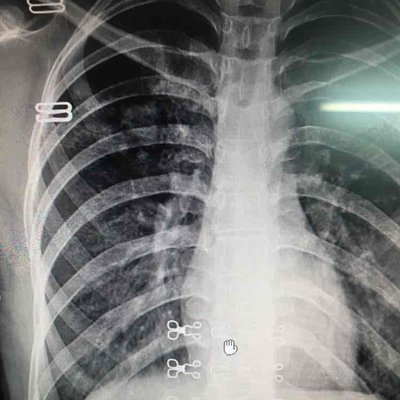

Bronchopneumonia is now a disease that many people will suffer from. There are many reasons leading to this disease, such as infection, immune deficiency, foreign body inhalation and so on. Only when we fully understand the cause of this disease can we have targeted prevention in our daily life. What is the cause of bronchopneumonia? Let's talk about it

Infection is the main cause of bronchopneumonia. If you suffer from tonsillitis and other diseases in your daily life, if you don't treat them in time, it will lead to further spread of inflammation. At this time, the human body's resistance is relatively low, so it is easy to be attacked by the disease bacteria, and then lead to infection, leading to bronchopneumonia, This is an important cause of bronchopneumonia, we must bear in mind.

The occurrence of bronchopneumonia is also closely related to the patient's own immune system. If the patient has immune deficiency, it is easy to lead to the occurrence of bronchopneumonia, and people with immune deficiency often have repeated symptoms of respiratory tract infection, which are the key to induce the occurrence of bronchopneumonia, Because the upper respiratory infection will lead to repeated suppurative lung infection, leading to the occurrence of bronchial pneumonia.

The causes of bronchopneumonia also include the inhalation of foreign bodies. If patients inhale foreign bodies in their daily life and do not deal with them in time, foreign bodies will exist in the airway for a long time, which is easy to cause lung infection and then bronchopneumonia, which is also an important cause of bronchopneumonia, We must try our best to avoid this disease in our daily life.